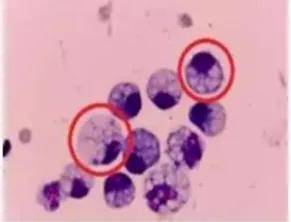

胃癌中的“伪装大师”

小雯所患的印戒细胞癌被称为“胃癌之王”,是胃癌中一种恶性程度极高的类型,占胃癌恶性肿瘤的10%左右。其名称来源于显微镜下观察到的肿瘤细胞形态——细胞内充满黏液,细胞核被挤压至边缘,形如一枚戒指。